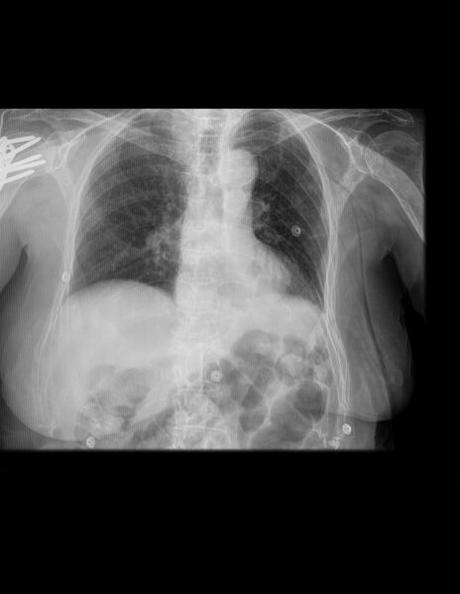

TÓRAX AP

LA PROYECCIÓN RADIOGRÁFICA OBTENIDA MUESTRA LOS SIGUIENTES HALLAZGOS:

Tejidos blandos simétricos, sin cambios en su densidad.

Silueta cardiomediastinica, con engrosamiento.

Botón aórtico, con calcificación.

Tráquea y columna vertebral central.

Hilios pulmonares, sin alteraciones.

Campos pulmonares, con patrón reticular difuso bilateral. Pulmón derecho, hacia lóbulo superior, probablemente en segmento III por topografía se observa imagen en anillo de sello, así como a nivel parahiliar inferior se observa imagen redondeada, irregular, bien definida, que mide 11 × 14 mm. Pulmón derecho, a nivel parahiliar existe imagen redondeada, irregular, bien definida, que mide 8 × 8 mm.

Senos cardio y costo frénicos bien definidos, sin identificar datos de derrame pleural.

A nivel de hombro derecho, con presencia de material de osteosíntesis. Resto de estructuras óseas, sin evidencia de lesiones líticas, blásticas o perdida de la contigüidad. Existen osteofitos marginales.

impresión diagnostica:

EN EL PRESENTE ESTUDIO RADIOGRÁFICO, CON IMÁGENES SUGERENTES DE NEUMOPATÍA CRÓNICA INTERSTICIAL, ASÍ COMO IMÁGENES SUGERENTES DE ADENOPATÍAS PARAHILIAR BILATERALES VS NÓDULOS PULMONARES, SIENDO LA DE MAYOR TAMAÑO DE LADO DERECHO.

MATERIAL DE OSTEOSÍNTESIS A NIVEL DE HOMBRO DERECHO.

ATEROESCLEROSIS Y CAMBIOS OSTEODEGENERATIVOS.

CORRELACIONAR CON DATOS CLÍNICOS Y ANTECEDENTES DE CONSIDERARSE NECESARIO POR MÉDICO TRATANTE, COMPLEMENTAR CON ESTUDIOS ADICIONALES O DE CONTROL, SEGÚN EVOLUCIÓN CLÍNICA DEL PACIENTE.